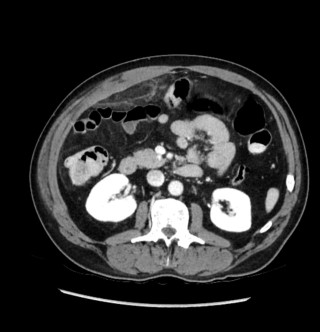

A 31-year-old previously healthy woman, with no surgical history, presented with sudden-onset, severe peri-umbilical abdominal pain unresponsive to high-dose opioids. CT-scan revealed mildly dilated distal jejunum with mesenteric edema and free fluid (Fig. 1, 2). Because of persistent pain despite step III analgesia, emergency diagnostic laparoscopy was performed. Intraoperatively, a closed-loop obstruction of an ileal segment was identified, herniated through a narrow internal window formed by an adherent mesenteric vessel supplying a Meckel’s diverticulum (Fig. 3). The vascular band was divided, releasing the closed loop, with no irreversible small bowel ischemic damage. The Meckel’s diverticulum was resected. The post-operative course was uneventful, and the patient was discharged after two days.